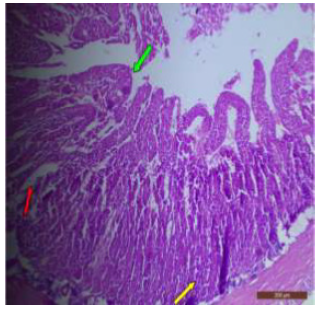

The duodenum of control rat showed histological features such as presence of different layers such as mucosa, submucosa, muscularis and serosa. The lining of epithelium of microvilli was composed of many cell types such as goblet cells, Paneth cells and absorptive columnar epithelial cells (Figure 1). Brünner’s glands were seen in the submucosal region of the duodenum which secrete alkaline fluid containing mucin (Figure 2). The rats treated with 600mg/kg b.w./day for 40 days revealed thickened and scattered villi (Figure 3). Hypertrophy of goblet cells and damaged crypts were also observed. (Figure 4). The necrotic Brünner’s gland showed inflammation and dilation of spaces (Figure 5).

Figure 1: T.S. of duodenum of control rat showing crypts (↑), closely packed microvilli (↑), well developed submucosa and muscularis externa. H&E × 100.

Figure 4: T. S. of duodenum of rat treated with 600 mg NaF/kg bw/ day for 40 days showing bulbous and swollen villus tip (↑), damaged crypts (↑) and hypertrophy of goblet cells (↑). H&E × 100.

In fluoridated rats damaged and broken villi, focal intervillous haemorrhages and ulceration was present (Figure 12). There was shortening and flattening of some of the villi (Figure 13), distorted crypts, large swollen goblet cells lined by columnar epithelium with wide spaces were present (Figure 14). Distortion of different layers of mucosa with the loss of villous architecture and shedding of surface epithelium was seen in the jejunum of fluoridated rats (Figure 15). The villus architecture was notably disturbed, with a marked loss of crypts. Furthermore, there was a noticeable decrease in the number of goblet cells (Figure 16). The villi appeared scattered and fragmented, indicating a disruption in their typical architecture. Reduction in size of intestinal glands highlighted the detrimental impact of fluoride exposure on the intestinal morphology of rats (Figure 17).

Figure 12: T.S. of jejunum of rat treated with 600 mg NaF/kg b.w./day for 40 days showing ulceration, focal intravillous hemorrhages and broken villi (↑). H&E × 100.

The ileal mucosa of control rat was built up of numerous folds forming the villi, through which connective tissue of the lamina propria containing tubular glands i.e., crypts of Leiberkühn were present (Figure 18). The epithelial lining of the villi was composed of Paneth cells and intestinal glands (Figure 19). In fluorotic rats, there were abnormal shaped, damaged and broken villi with bulbous tips. Lymphatic dilation and haemorrhaged in lamina propria were also seen (Figure 20). In the ileal mucosa, prominent inflammation, distortion of crypts with shredded cells inside the crypts were visible (Figure 21). Swollen and necrotic crypts were present (Figure 22). The ileal tissue showed disruptions in the normal mucosal architecture with signs of villous atrophy and cell infiltration (Figure 23). Lymphatic infiltration was prominent and numerous enlarged lymph nodules appeared in lamina propria of villi. There were ill-defined cell boundaries, vacuolated cytoplasm and pyknotic nuclei (Figure 24).

Figure 13: T.S. of jejunum of rat treated with 600 mg NaF/kg b.w./day for 40 days showing distortion, shortening and flattening of villi (↑). H&E × 100.

Figure 16: T.S. of jejunum of rat treated with 600 mg NaF/ kg b.w./day for 40 days showing disruption of villi (↑), reduction in number of goblet cells (↑) and crypt loss (↑). H&E × 100.

Figure 17: T.S. of ileum of control rat showing scattered and broken villi (↑) and decrease in size of intestinal glands (↑). H&E × 100.